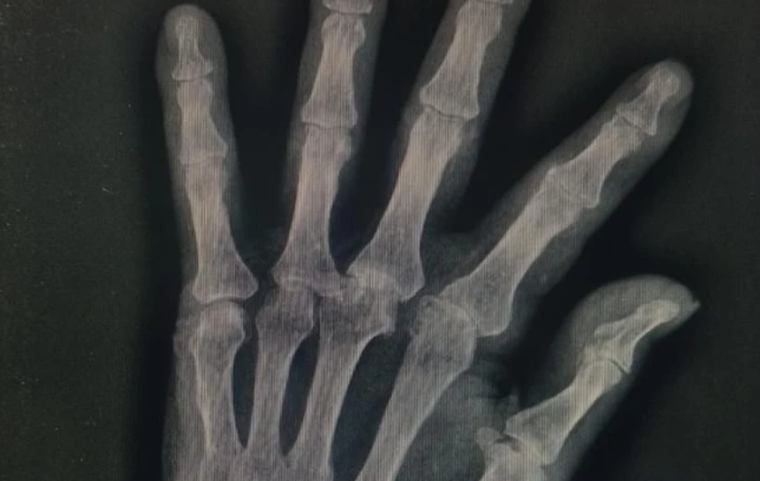

En la misma publicación, la familia difundió imágenes del adulto mayor con lesiones visibles y fragmentos de los videos de seguridad del geriátrico. También compartieron radiografías realizadas posteriormente, en las que se constataron fracturas en la mano derecha, en particular en el dedo pulgar, además de heridas en el rostro.